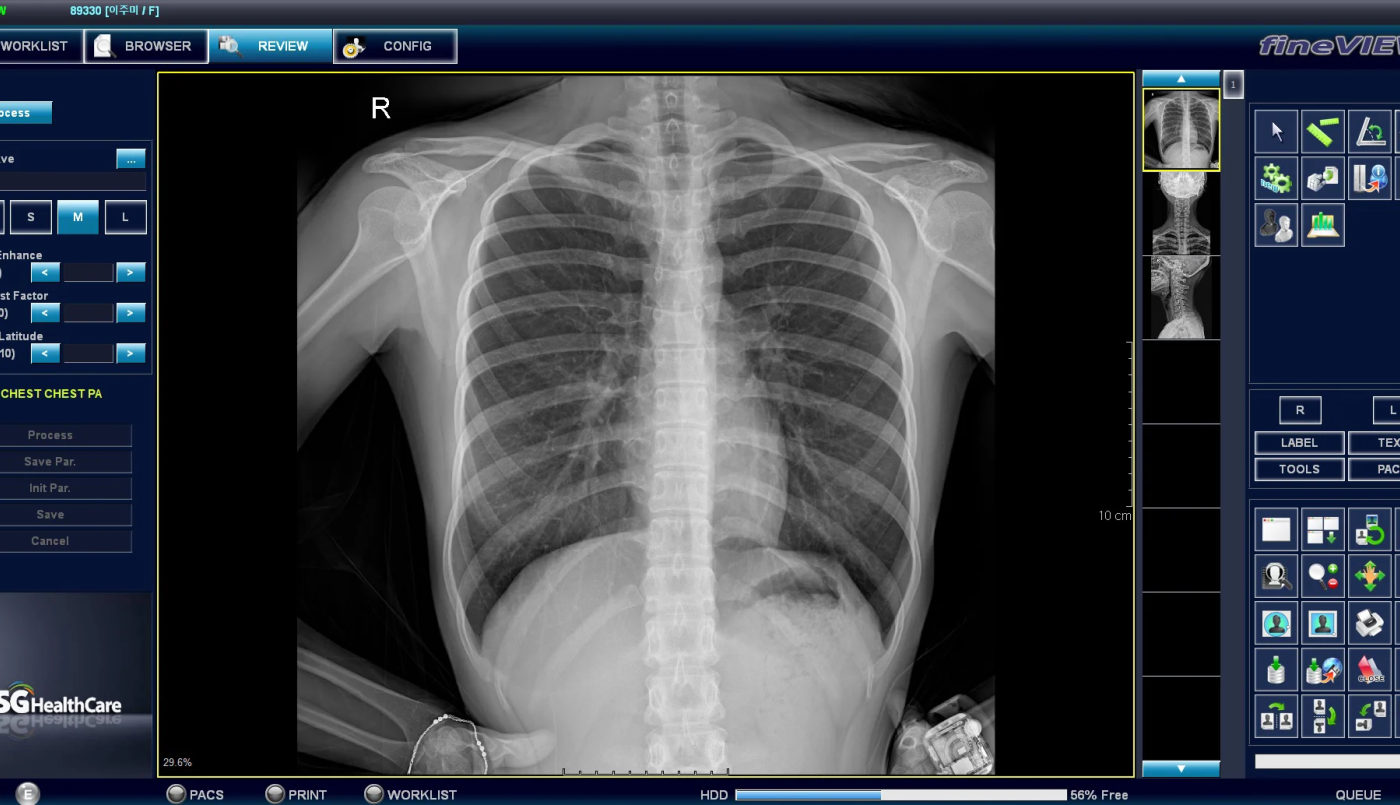

En el marco de su política de inversión en tecnología para mejorar la calidad del servicio en los efectores provinciales, el gobierno de Santa Fe, a través del Ministerio de Salud, licitó la compra de 40 digitalizadores de placas radiográficas para hospitales y centros de salud de segundo nivel.

La licitación, que tiene un presupuesto oficial de $ 876.000.000, permitirá actualizar la tecnología para la obtención de imágenes de radiografía en 38 localidades de la provincia. En esta primera etapa, se alcanzará al 50% de los efectores de segundo nivel que todavía utilizan el revelado convencional, un método obsoleto y con insumos cada vez más escasos.

Mayor calidad de imagen: Las imágenes digitales son más nítidas y precisas que las obtenidas con el método tradicional de revelado, lo que permite un mejor diagnóstico de las enfermedades.